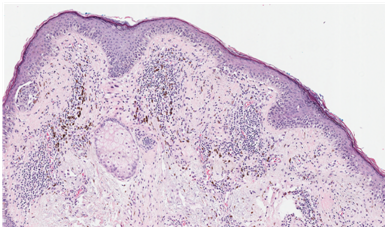

Following institutional review board-authorization, 13 primary cutaneous melanomas and 19 nevi were retrieved (5 common nevi, 5 mild dysplastic, 4 moderate dysplastic, and 5 severe dysplastic), (Figures 1-3). 5-μm formalin-fixed, paraffin-embedded sections were cut and mounted onto positively charged slides. Single IHC S100A9 staining was performed using the Leica Bond III protocol. All antibodies were purchased from Leica Biosystems (Buffalo Grove, IL). A board certified dermatopathologist evaluated S100A9 staining of melanocytes and keratinocytes in the epidermis of each sample. The pattern of staining was classified according to one of three categories: diffuse epidermal staining Figure 4, linear basement membrane staining Figure 5, and irregular patchy epidermal staining Figure 6.

Figure 2 H&E stain of mildly dysplastic nevi of lesion B(hematoxylin and eosin, 40x).

Figure 5 Linear S100A9 stain of mildly dysplastic nevi of lesion B.